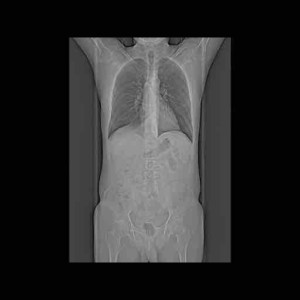

Eersts voor de nerds:

Dan foto’s die voor hen blijkbaar belangrijk zijn.

Nog een overzicht.